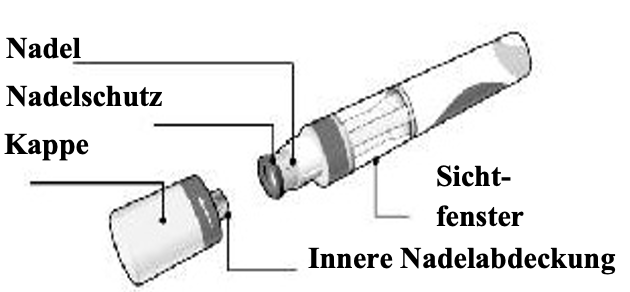

Abbildung des Cosentyx 150 mg SensoReady Pen mit entfernter Kappe. Entfernen Sie die Kappe erst, wenn Sie für die Injektion bereit sind.